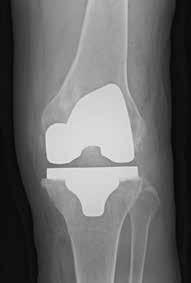

(Top, from left) X-ray images show a normal knee; unicompartment OA with some wearing on inner side of knee; and post-partial knee replacement.

(Bottom, from left)

Tricompartment OA with severe damage to both knees; and post-total knee replacement.

Total knee replacement

TKR, also known as total knee arthroplasty, is a surgical procedure to replace the damaged or diseased knee joint with an artificial implant. It involves removing damaged bone and cartilage from the knee joint and replacing them with

metal and plastic components that mimic the natural knee joint.

TKR is typically recommended for patients with OA affecting the entire knee joint, significant deformity, or extensive damage to the three areas, or compartments, of the knee. It may also be recommended for patients with inflammatory arthritis, post-traumatic arthritis, or other conditions causing severe knee pain and functional impairment.

The success rates for TKR are generally high, but outcomes depend on patients’ age, overall health, severity of the arthritis, and rehabilitation compliance, said Dr Liu. “TKR implants are designed to last for many years, with the majority lasting 20 years or more,” he said.

TKR can significantly improve knee pain, function and mobility, and quality of life for many patients, while risks include infection, blood clots, implant loosening, stiffness, and nerve damage.

SGH performs more than 3,000 TKR surgeries each year, about half the 6,000 done every year in Singapore, Dr Liu said. TKR is performed as a day surgery at SGH for most patients.